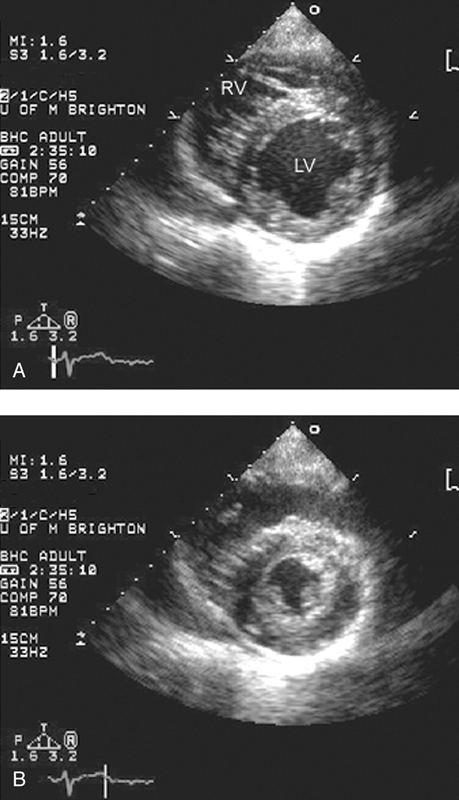

فحوصات تشخيصية لبعض امراض القلب والشرايين التاجية